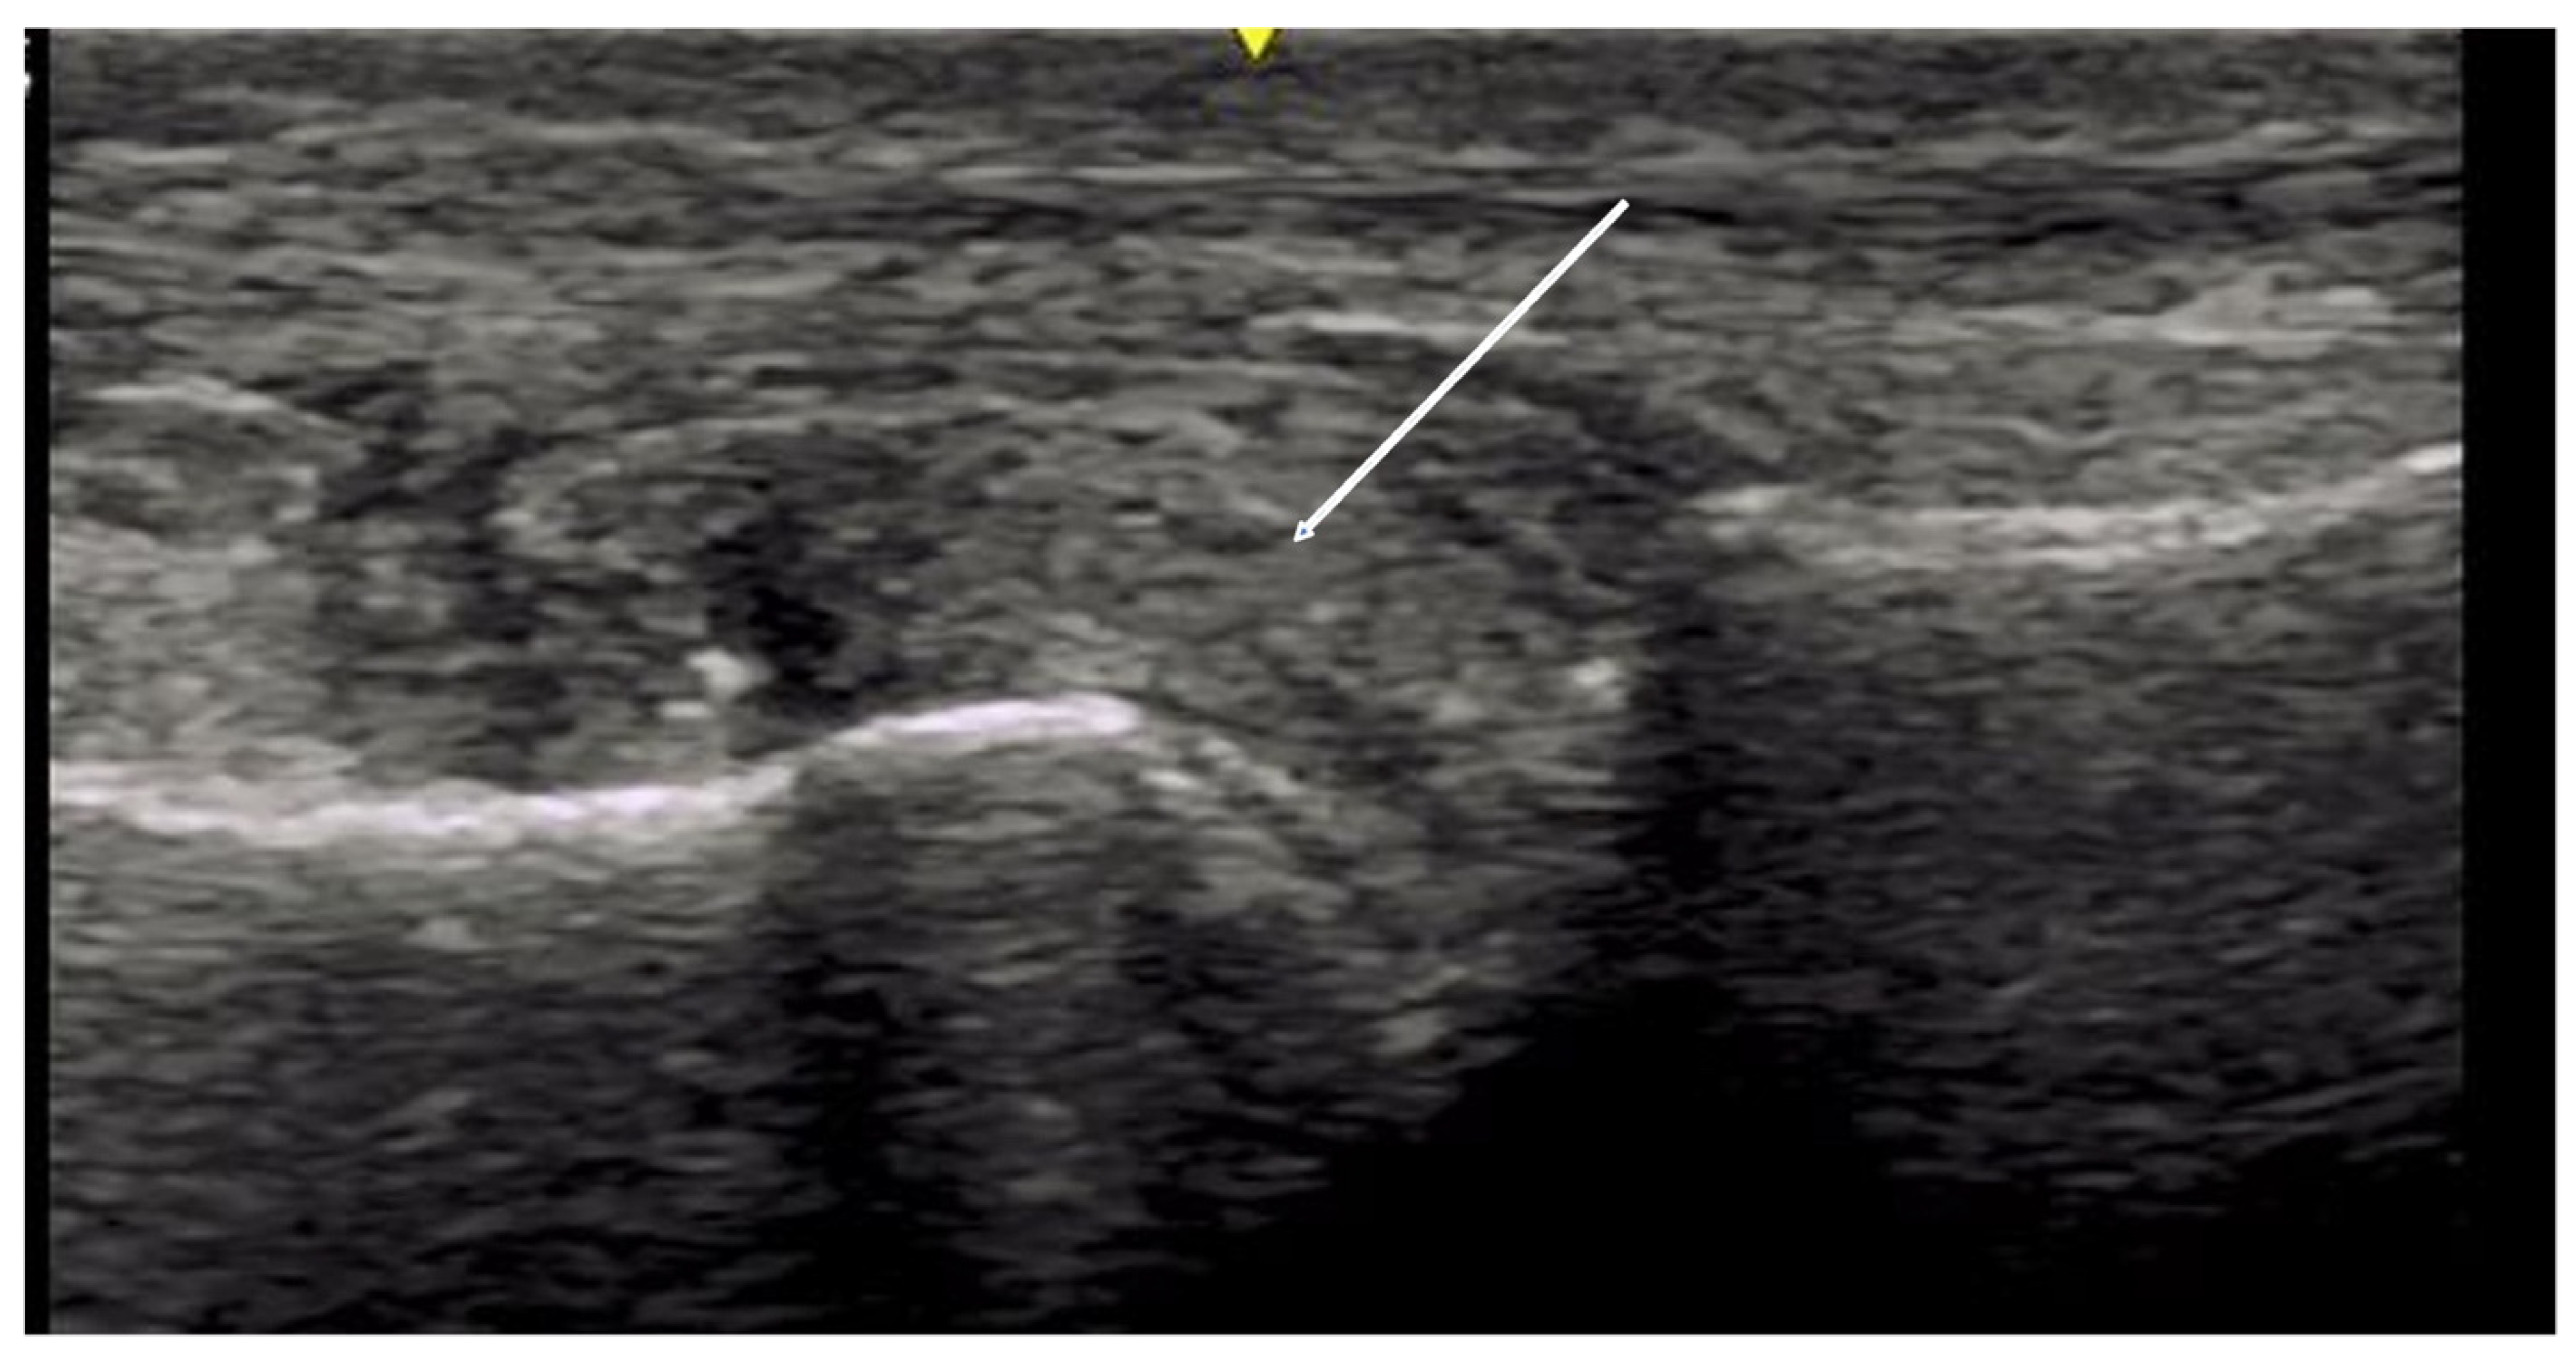

2.1.3. Acro-Osteolysis

2.2. Tendon Pathology

2.2.2. Contractures and Tendon Friction Rubs